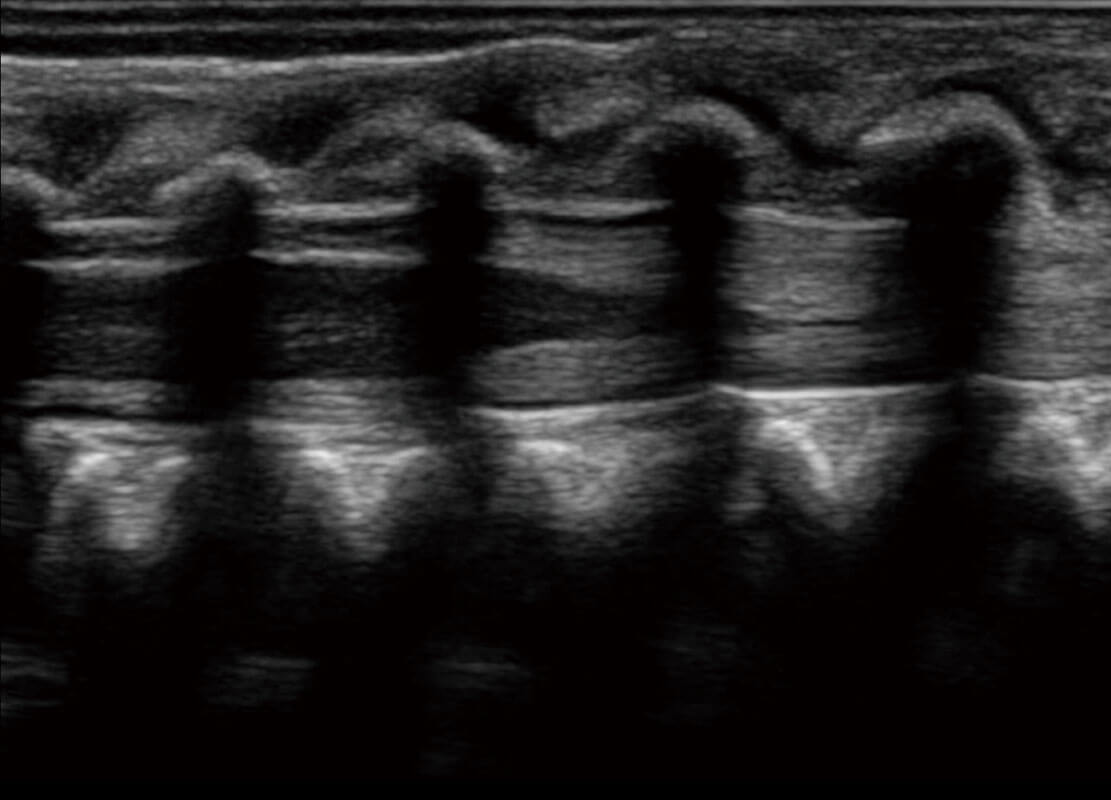

P60搭载宽频带线阵探头、宽景成像、弹性成像技术,为您提供乳腺应用方案。P60支持高频相控阵探头、线阵探头、腹部高频探头、腹部微凸探头等,丰富的探头群搭载敏感的彩色血流成像,适用于新生儿多种脏器检测要求,满足新生儿筛查需求。

新生儿肝血管癌

新生儿脊髓圆锥

新生儿心脏